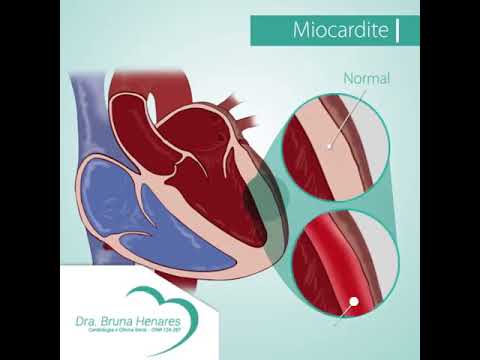

Miocardite Youtube Miocardite é a inflamação do músculo cardíaco. geralmente ocorre após infecções virais, principalmente após quadros gripais ou de sintomas gastrointestinais. A miocardite é a inflamação do miocárdio, o músculo cardíaco, que pode resultar em alterações temporárias no coração – e até mesmo permanentes nos casos mais.

Miocardite Youtube Entre em contato com o dr cotta jr: espacovitacardio .br dr cotta jr sob. Saiba como diagnosticar a insuficiência cardíaca de forma clínica e a importância do ecocardiograma nesse processo. descubra se essa condição pode ser curada ou controlada. tratamento da miocardite e infarto agudo do miocárdio (0:48). A miocardite aguda é uma inflamação do tecido muscular do coração, que pode ter várias causas. mas após o diagnóstico, o paciente pode ter uma rotina normal? quais devem ser os cuidados?. Descubra o que é miocardite aguda, suas causas, sintomas, diagnóstico, tratamento e prevenção. saiba mais sobre esta condição cardíaca aqui.

Miocardite Youtube A miocardite aguda é uma inflamação do tecido muscular do coração, que pode ter várias causas. mas após o diagnóstico, o paciente pode ter uma rotina normal? quais devem ser os cuidados?. Descubra o que é miocardite aguda, suas causas, sintomas, diagnóstico, tratamento e prevenção. saiba mais sobre esta condição cardíaca aqui. O cardiologista dr. fábio fernandes te fala mais sobre o que é a miocardite, quais seus sintomas e possíveis tratamentos!. Resumo sobre miocárdio de acordo com o ministério da saúde, o infarto agudo do miocárdio destaca se como a maior causa de mortes no país. a miocardite caracteriza se por ser uma resposta inflamatória do miocárdio. A miocardite é uma inflamação do músculo cardíaco (miocárdio), que normalmente surge como complicação durante diferentes quadros no organismo e pode afetar o sistema elétrico do coração, reduzindo a capacidade do órgão de bombear o sangue de forma correta, o que causa ritmos cardíacos acelerados ou anormais, conhecidos como arritmias. Saiba mais . pronto atendimento. conheça a classificação de prioridade do nosso pronto atendimento: sobre nós. quem somos; estrutura; qualidade; humanização e voluntariado; grupo marista; instagram facebook linkedin. crm 5522 pr | jarbas motta júnior | responsável técnico médico | crm pr 26227 | rqe 19368.